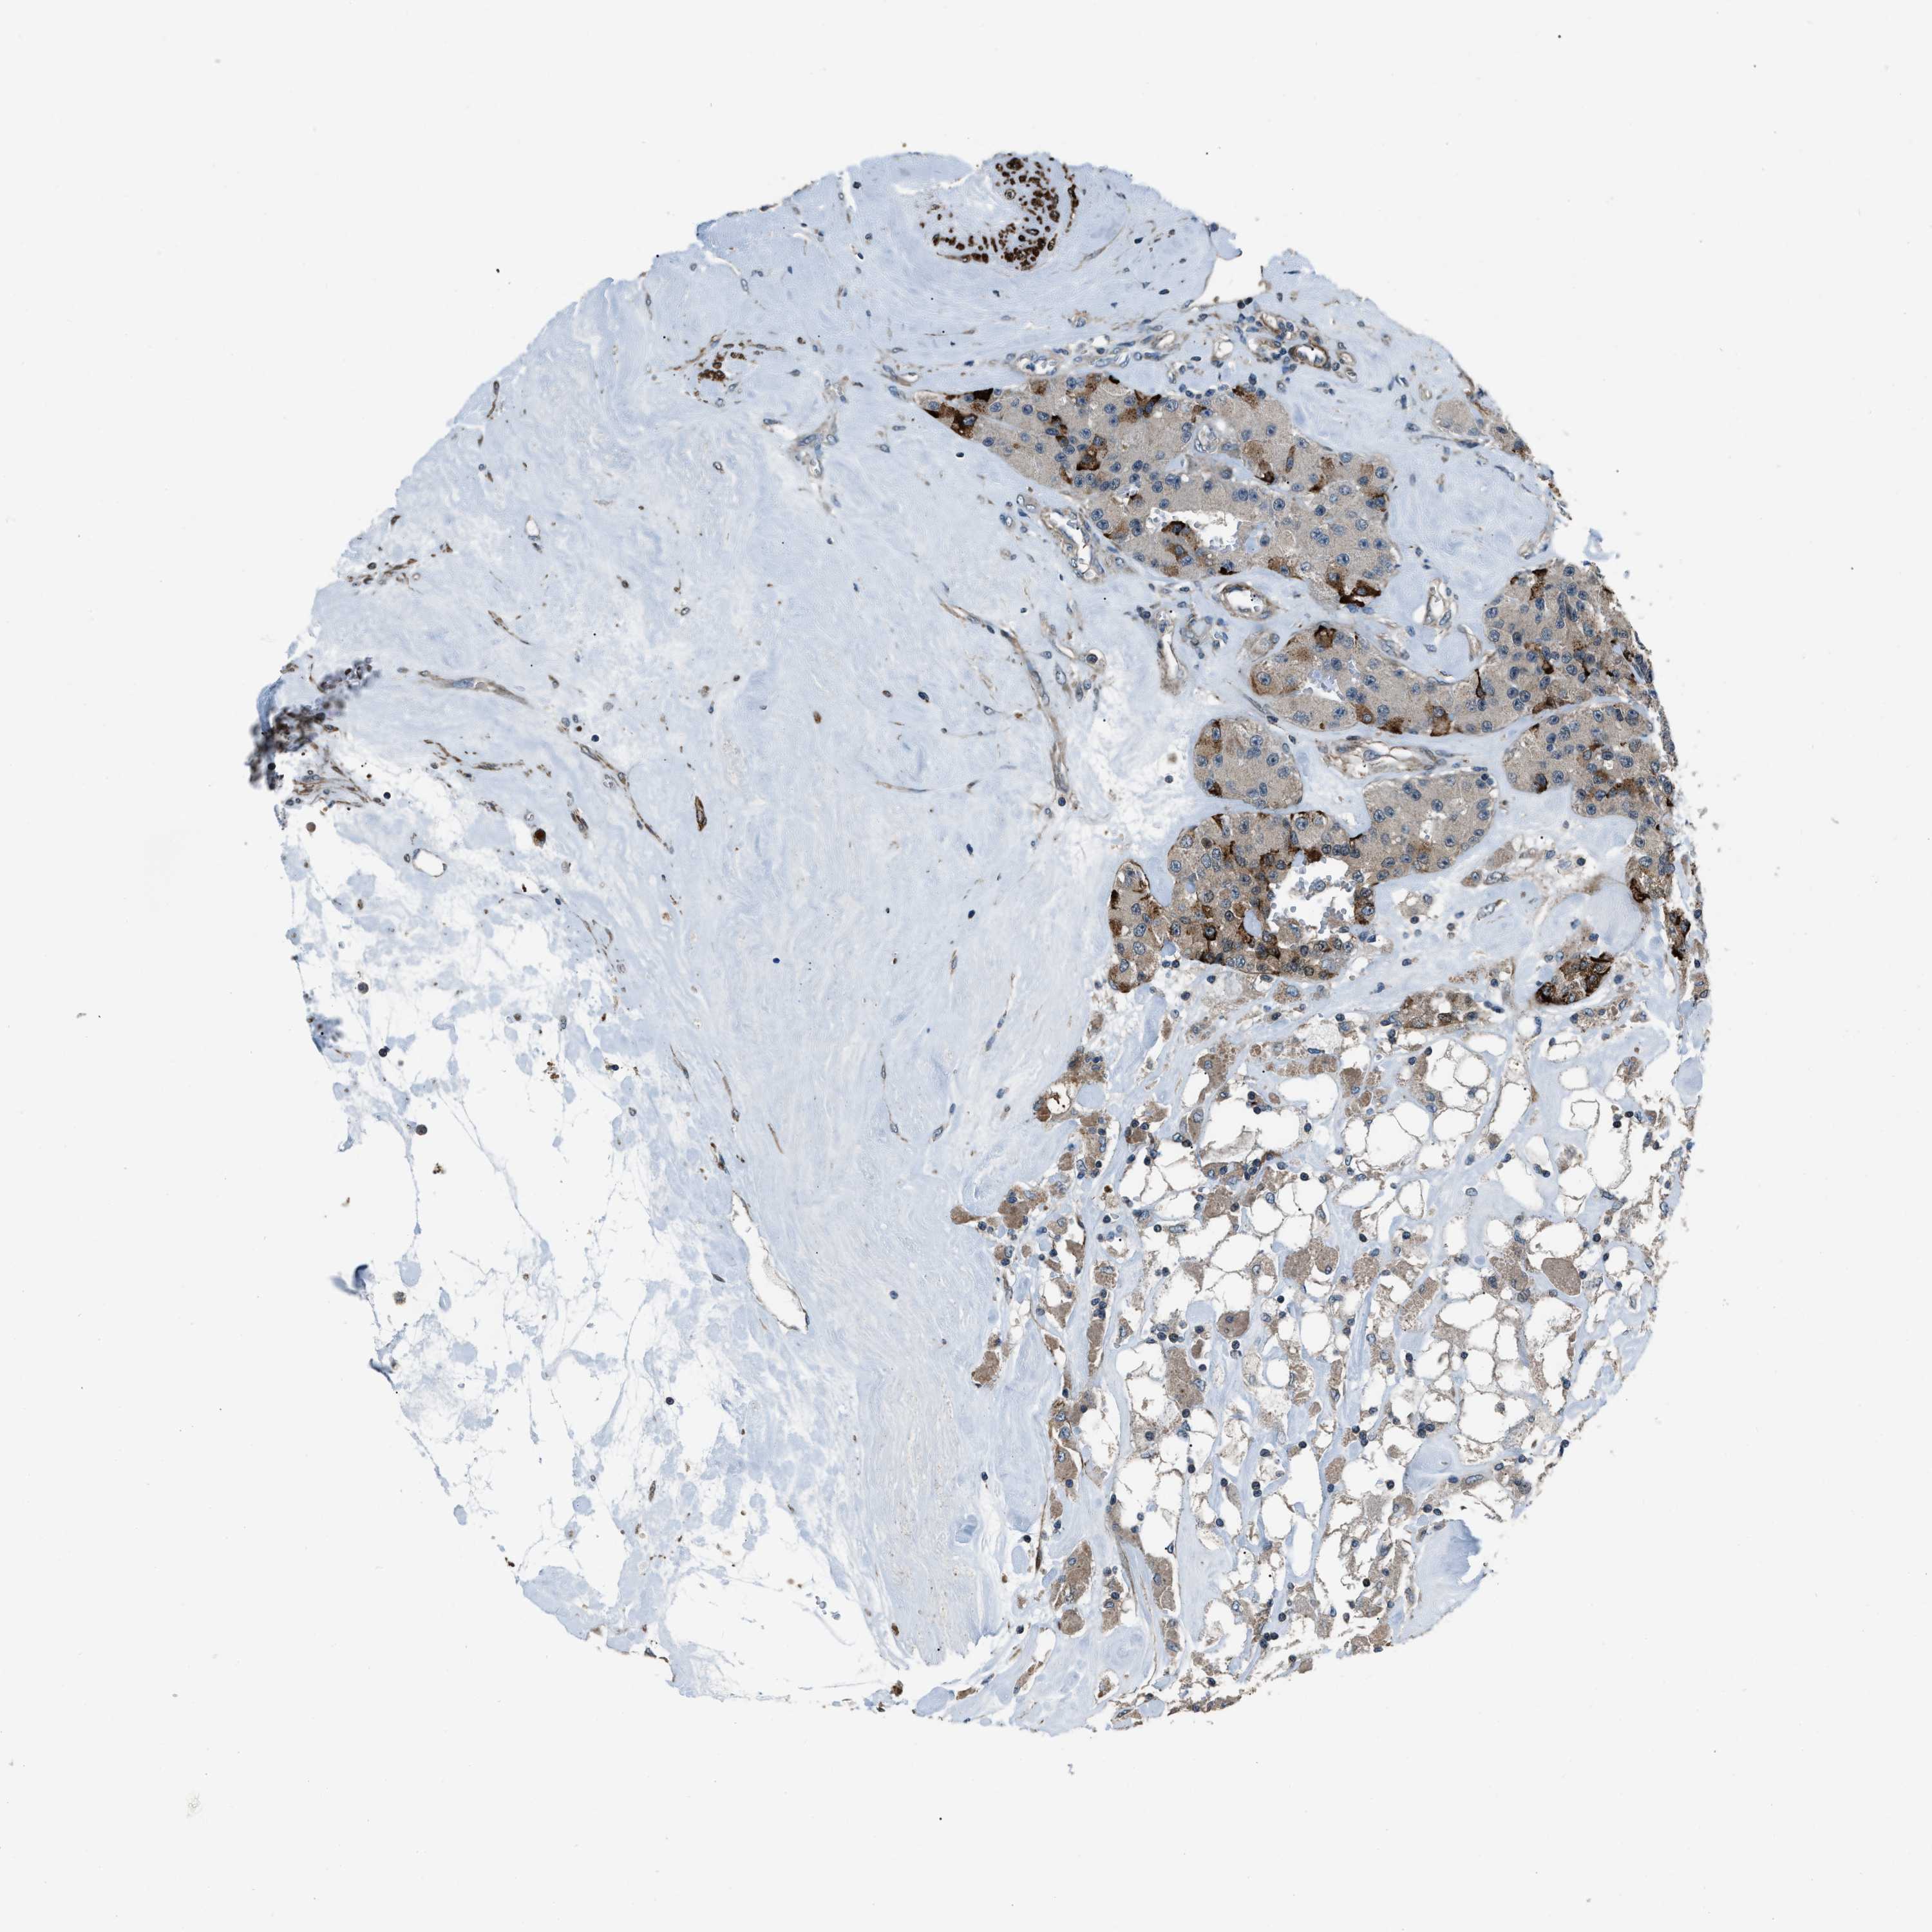

CARCINOID - Protein expressioni

A mouse-over function shows sample information and annotation data. Click on an image to view it in a full screen mode. Samples can be filtered based on level of antibody staining by selecting one or several of the following categories: high, medium, low and not detected. The assay and annotation is described here.

Antibody stainingi

Antibody staining in the annotated cell types in the current human tissue is reported as not detected, low, medium, or high, based on conventional immunohistochemistry profiling in selected tissues. This score is based on the combination of the staining intensity and fraction of stained cells.

Each image is clickable and will lead to virtual microscopy that enables deeper exploration of all samples and also displays staining intensity scores, fraction scores and subcellular localization as well as patient and tissue information for each sample.

Antibody HPA019136

Antibody HPA019528

Antibody HPA019529

Staining

High

Medium

Low

Not detected

Intensity

Strong

Moderate

Weak

Negative

Quantity

>75%

75%-25%

<25%

None

Location

Nuclear

Cytoplasmic/membranous

Cytoplasmic/membranous,nuclear

Carcinoid, malignant, NOS

Carcinoma, NOS